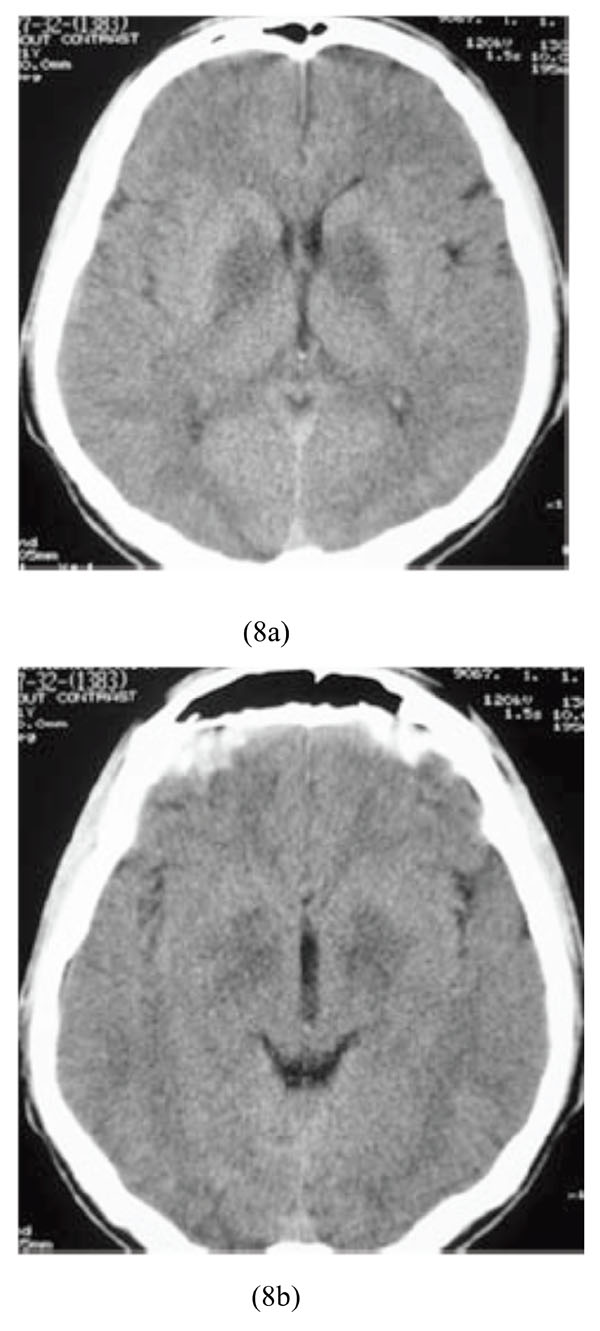

A 21-year-old male farmer was admitted because of suicidal ingestion of organophosphate toxin. His symptoms started with sweating, headache, nausea and vomiting, muscular weakness, and dizziness. Upon admission, he had pin-point pupils which followed by loss of consciousness, urinary incontinence and finally seizure. His vital signs were as follows: BP=90/60, PR=50/min, RR=12/min. Brain CT scan showed bilateral hypodensity lesions of the basal ganglia indicative of infarctions (Figs. 8a-8b).

Bilateral hypodensity lesions of the basal ganglia indicative of infarctions following ingestion of organophosphate toxin.